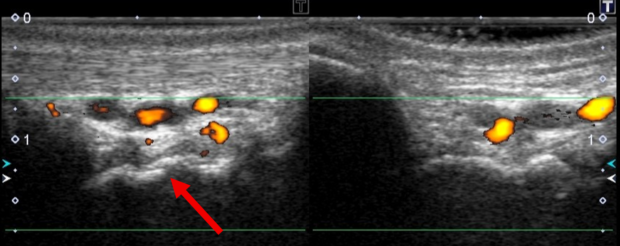

こんな感じで、舟状骨の

などで詳しく検査したところ、

※左(患側:右手)、右(健側:左手)

骨の連続性が断たれたことを疑わせる、エコー画像が描出され、

患側の血流増加(炎症反応)も確認されました。

これらのことから舟状骨骨折が疑われました![]()